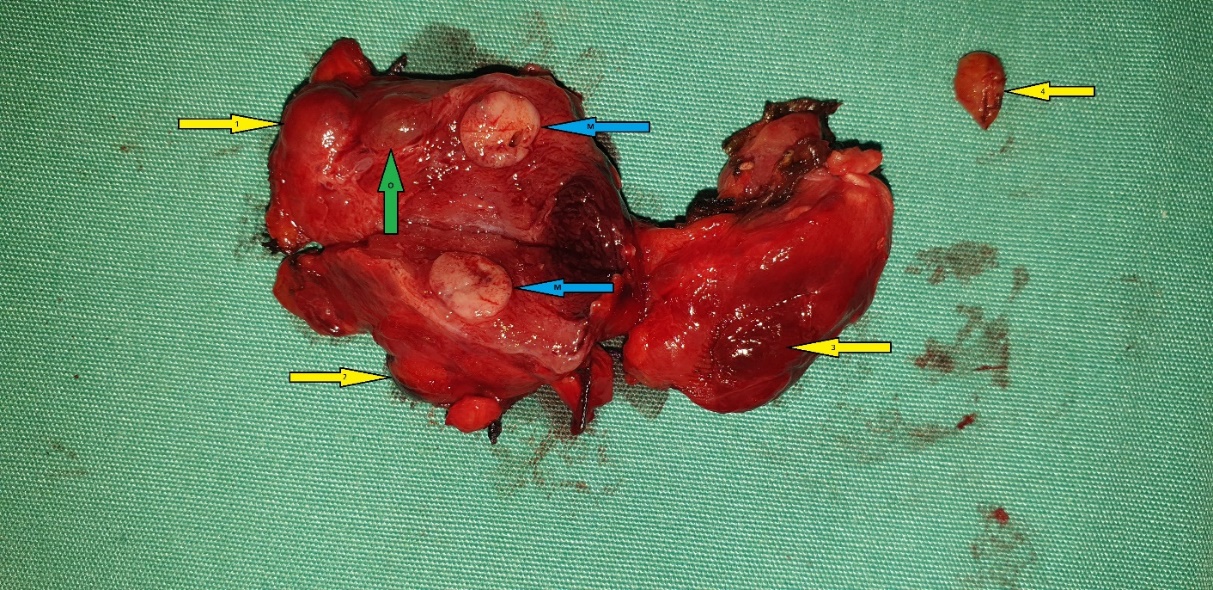

Figure 5 . Surgical specimen a) Blue arrows: encapsulated medullary microcarcinoma b) Yellow arrows : parathyroid glands . c) Green arrow : Benign thyroid nodule . ( Courtesy Dr . V . Penopoulos ) .